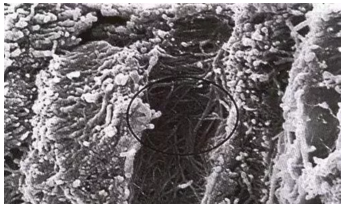

圖中上半部分牙本質(zhì)采用37%磷酸酸蝕15秒徹底沖洗后牙本質(zhì)橫斷面,可見玷污層已經(jīng)被去除(放大倍數(shù)1000)